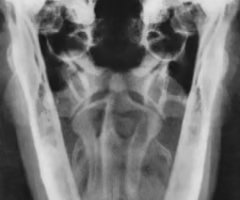

Identify the species?

Feline

-ribs thin

-vertebrae long/rectangular

Canine

-Thick blocky vertebrae